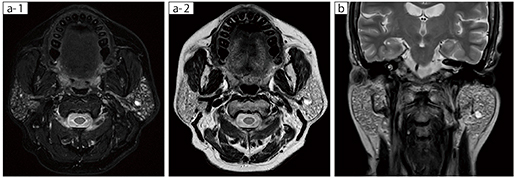

■症例2:シェーングレン症候群

60歳代,女性。左顎下部に違和感があり受診。他院からの紹介にて検査実施。FatSepの脂肪抑制を使用することで,安定的に脂肪を抑制できている。また,FatSepで撮像することで,T2強調画像と脂肪抑制画像の2種類の画像を同時に取得できるため,検査時間を短縮することが可能である。

a-1:FatSep T2WI,a-2:T2WI(Multi Contrast)

TR/TE=5254/75,スライス厚:4mm,FOV:180mm

b :T2WI,TR/TE=4000/85,スライス厚:4mm,FOV:240mm